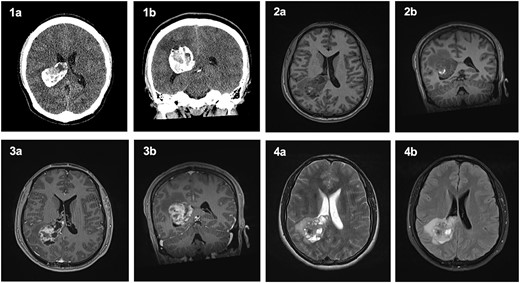

A non-contrast computed tomography (CT) head revealed a 4 × 5 × 5.3 cm3 lesion within the trigone of the right lateral ventricle (Fig. 1). The lesion was largely calcified and had a cystic component. Associated cerebral oedema was noted in the periventricular deep white matter of the right parietal and temporal lobes. There was no evidence of midline shift, and the basal cisterns remained patent. A magnetic resonance imaging (MRI) scan showed a lesion in the trigone of the right lateral ventricle, which was mostly isointense on T1-weighted imaging, with a focus of hyperintensity in the centre of the lesion. On T2- weighted imaging, the lesion was isointense. Upon administration of gadolinium, there was irregular enhancement of the lesion, with scattered, non-enhancing regions (Fig. 1).

Computed Tomography and Magnetic Resonance Imaging showing a mass within the trigone of the right lateral ventricle. On CT, axial (1a) and coronal (1b) sections revealed a calcified mass with a central cystic component. Pre-contrast T1-weighted imaging showed an isointense mass with a central ring of enhancement on axial (2a) and coronal (2b) slices. Post-contrast T1-weighted imaging with irregular enhancement of the lesion on axial (3a) and coronal (3b) slices. Axial T2-weighted imaging (4a) and FLAIR (4b) exhibited an isointense lesion with surrounding oedema.